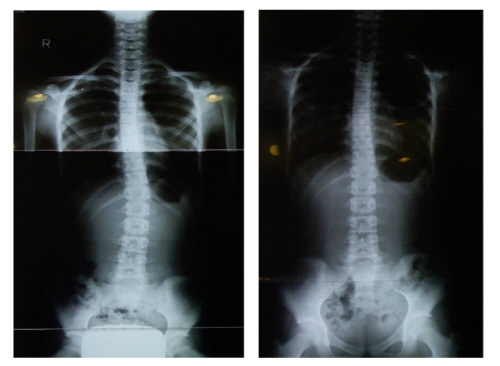

ôÃßÃø¸¸ÁõÀÌ ÀÇ½ÉµÈ´Ù¸é ±Ùó Á¤Çü¿Ü°ú¿¡¼ X-RAYÃÔ¿µÀ» ÅëÇÑ Ã´ÃßÃø¸¸ÁõÀÇ ¹ßº´¿©ºÎ¸¦ ÆÄ¾ÇÇϰí, ¾î¶² ¹æ¹ýÀ¸·Î Ä¡·á ÇÏ´ÂÁö°¡ °¡Àå Áß¿äÇÏ´Ù. ƯÈ÷ 16¼¼°¡ µÇ±â Àü¿¡ ôÃßÃø¸¸Áõ Áø´ÜÀ» ¹ÞÀº°æ¿ì, ¼ºÀÎÀÌ µÇ¸é ÈÖ¾îÁüÀÇ °¢µµ°¡ Á¡Á¡ ´õ Ä¿Áú ¼ö ÀÖ¾î Á¶±âÄ¡·á°¡ ÇʼöÀûÀÌ´Ù.

Àκ»º´¿ø ôÃß¼¾ÅÍ ¼ÛÇü¼® ¿øÀåÀº ¡°Ã´ÃßÃø¸¸ÁõÀº Á¤È®ÇÑ Áø´Ü°ú Ä¡·á¸¦ ¹ÞÀ» ¼ö ÀÖ´Â º´¿ø¿¡ ³»¿øÇÏ´Â °ÍÀÌ ÁÁÀ¸¸ç, ¹æÄ¡ÇÏ¸é ¾ÇÈµÉ È®·üÀÌ ³ô¾Æ X-RAY°Ë»ç ÈÄ Á¶±âÄ¡·á°¡ Áß¿äÇÏ´Ù¡±¶ó°í Á¶¾ðÇß´Ù.